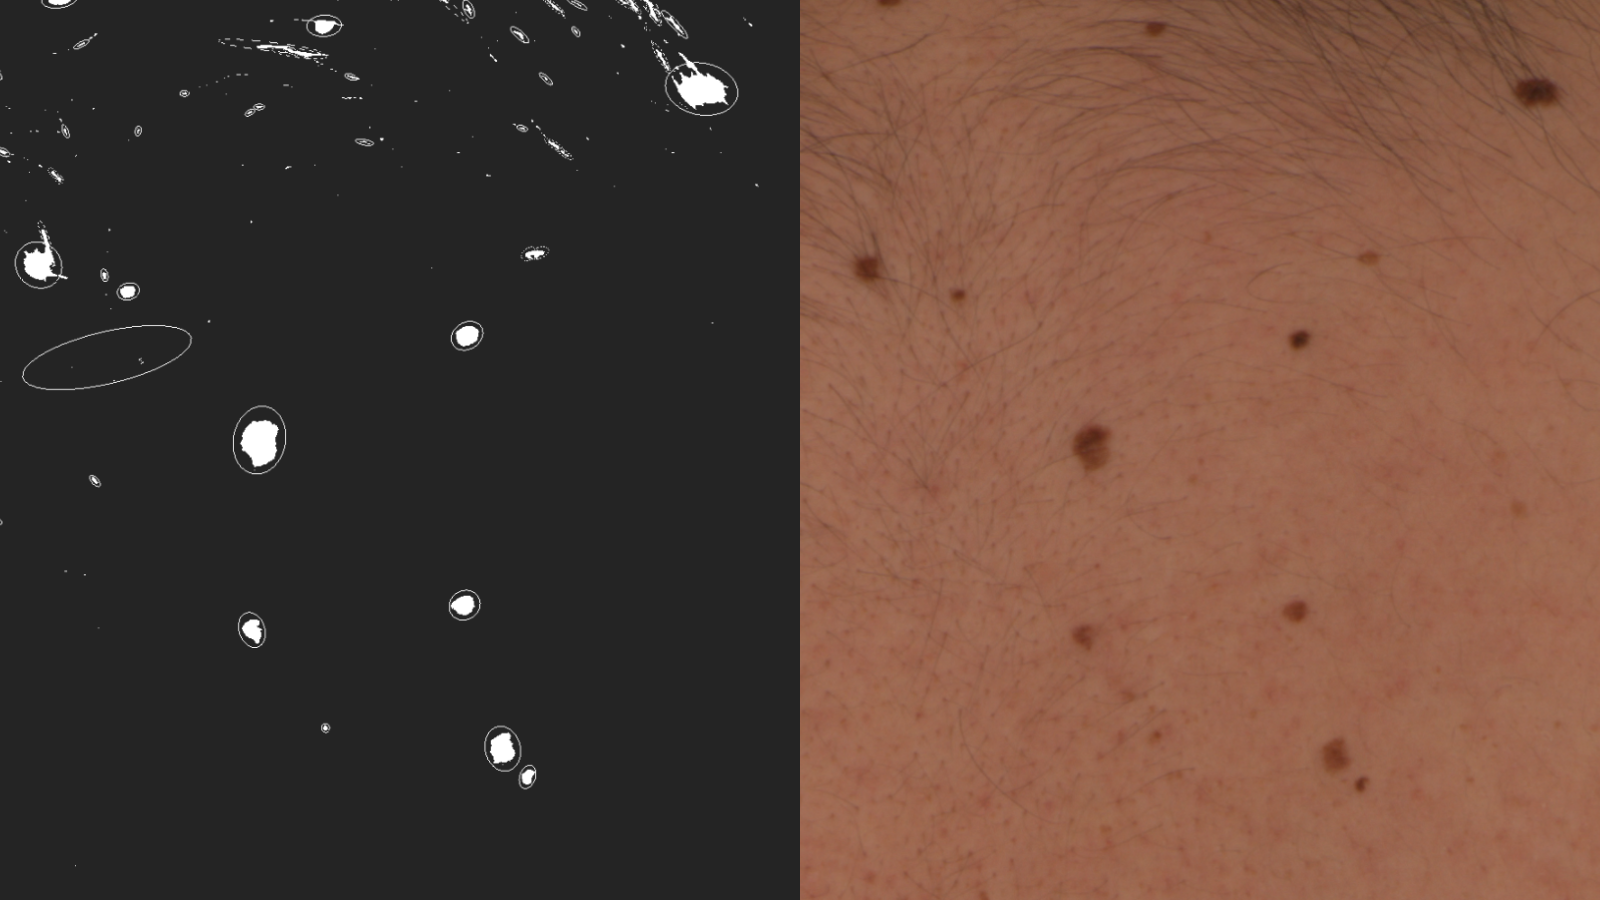

The MoleGazer project aims to combine astronomical data analysis with full body photography used by dermatologists to monitor patients. Within the project, a patient’s skin is treated like the background sky in an astronomical image, and any moles are treated as stars. This analogy allows for automated identification and analysis of moles as they evolve over time.

Caption: A side by side comparison of moles on a patient's back (right) and the same moles as star-like targets in the astronomical software used by the MoleGazer team (left).

Credit: The MoleGazer Team